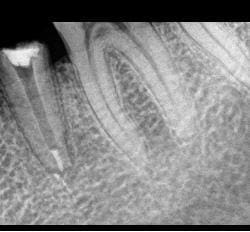

Patient de 35 ans, a fait la CCM sur 35 il y a Deux mois.

Arrive car douleur insupportable à la mastication.

A peine j'appuie légèrement, il saute au plafond.

Je dépose la couronne et le (volumineux !!) inlay core.

Toujours douleur à la pression quand j'appuie sur la racine.

Je ne vois que deux explications :

- Desmodontite par trauma occlusal (mais pas de poche !) ou surocclusion quelquonque (mais l'occlusion semble bien apres controle avec papier d'occlusion)

- Félure ou fracture ( vous voyez qqchose de suspect à la radio ?) mais la encore pas de poche...j'ai essayé la trasillumination je n'ai rien vu mais en meme temps vu l'effet de coin provoqué par l'inlay core présent.c'est possible quand meme..

Une autre radio, après dépose...

A l'apex vous ne voyez pas comme l'apex avec fracture horizontal ? en meme temps je l'ai trop regardé cette radio, elle m'aveugle !